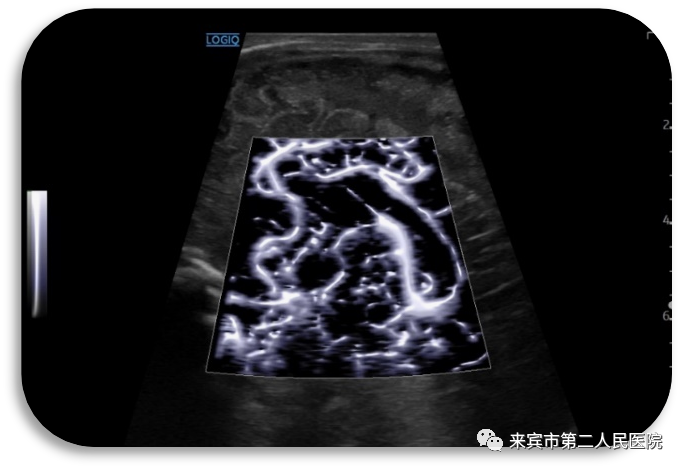

5.立体血流成像,呈现3D效果,有助于更清晰显示微小病灶,淋巴结等微细血流灌注,帮助临床精准诊断。